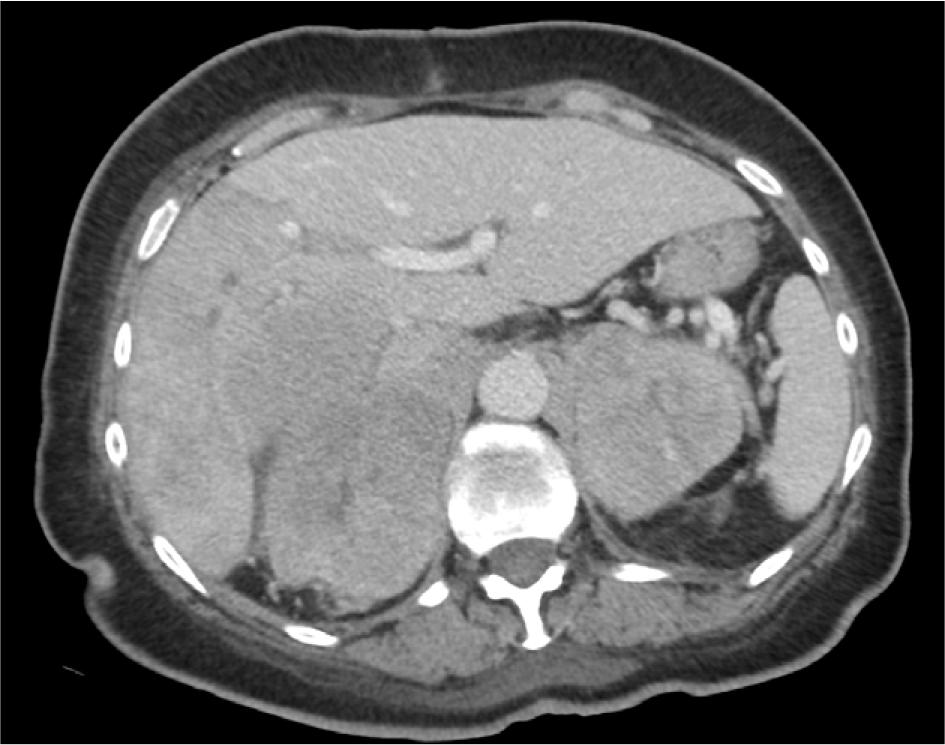

CT, contrast-enhanced, axial plane – the image shows bilateral polycyclic adrenal masses with heterogeneous enhancement. The left adrenal mass infiltrates the left diaphragm crus. On the right side, the mass most likely infiltrates the inferior vena cava and adheres to lesions in the liver.